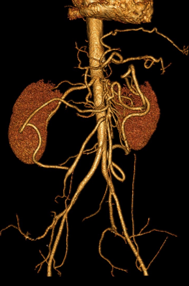

Pathologie digestive - grêle et colon, imagerie et pathologie